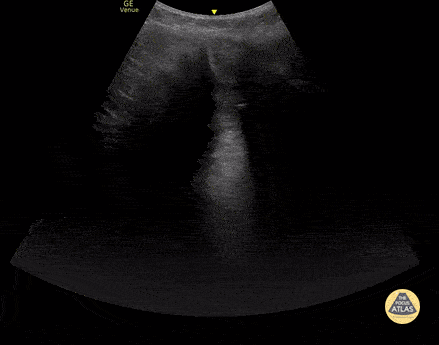

Healthy 13 year old presented with 2 days of epigastric and RUQ pain, with tenderness in the RUQ on exam. Biliary POCUS was performed with a low frequency, curvilinear transducer. She had a positive Murphy's sign. In the transverse view, the gallbladder is demonstrated with a thickened wall and with adjacent hypoechoic collections suggestive of pericholecystic fluid. She underwent ERCP, was found to have a common bile duct stone, and ultimately went for cholecystectomy. Contributor: Allie Grither, MD, St. Louis Children's Hospital (Washington University in St. Louis), @AGPemMD